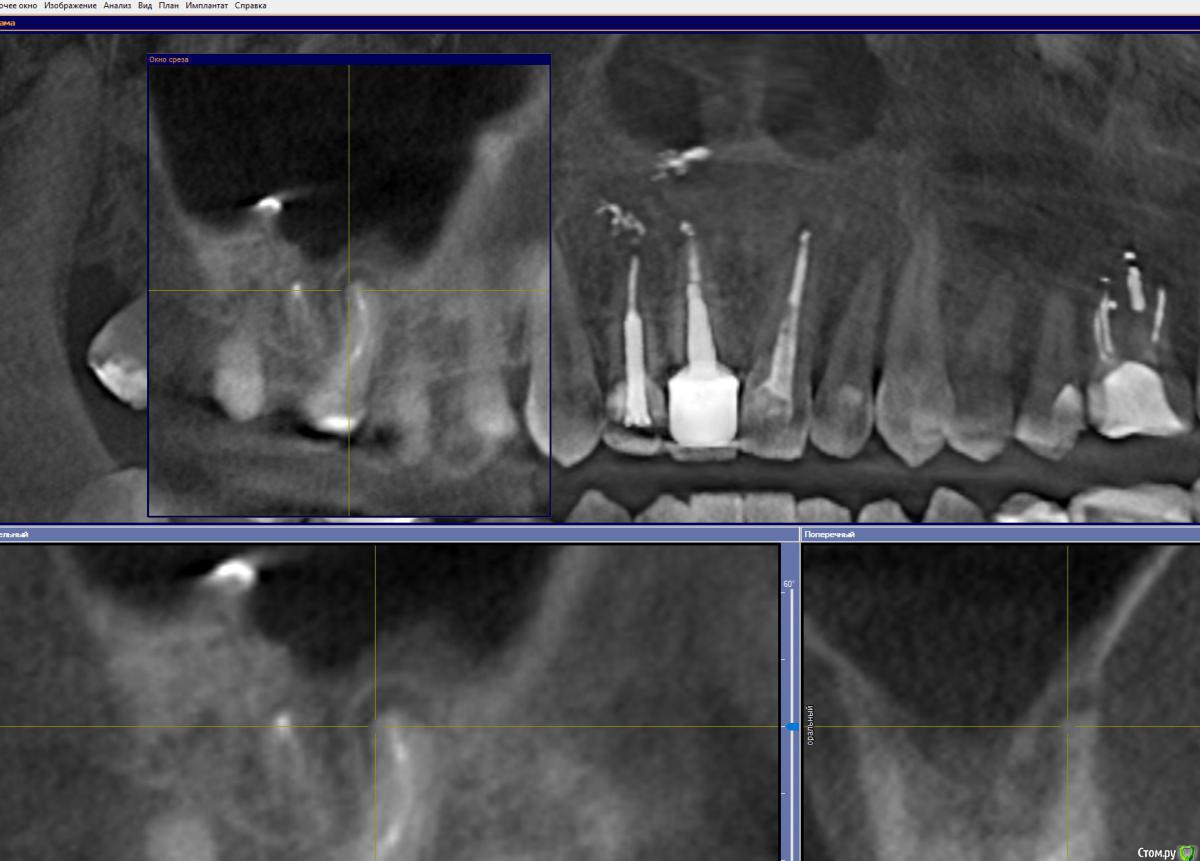

GoldJoker Опубликовано 11 декабря, 2017 Поделиться Опубликовано 11 декабря, 2017 Сломан инструмент/Киста - Удалять, резекция, пробовать достать инструмент. 16 зуб. Шестерка.Говорят при попытке достать можно протолкнуть инструмент. Как считаете пробовать доставать под микроскопом, резекция или сразу удалять?После грипа дискомфорт в десне над зубом, чувствую воспаление. Срезы прикрепил. Ссылка на комментарий

GoldJoker Опубликовано 11 декабря, 2017 Автор Поделиться Опубликовано 11 декабря, 2017 Срезы не информативны, но я за лечениеИнструмент за изгибом думаете достать пробовать? Добавляю срезы. Просто что делать если его выбьют за верхушку корня при попытки достать его ультразвуком?http://joxi.net/V2VvZN4SxPvbO2http://joxi.ru/xAeXqnbIpGl9D2 Ссылка на комментарий

GoldJoker Опубликовано 3 февраля, 2018 Автор Поделиться Опубликовано 3 февраля, 2018 нет Иду на перелечивание, если не удастся удаление. Такой вопрос там в пазухе кусочек пломбировочного. Один имплантолог говорит не надо его трогать. Другой предлагает убрать за раз во время удаления доступом с десны, мол там же потом делать будет синус лифтинг расширил ту дырку. Как думаете удалять тот кусочек или нет и делать синус лифтинг не трогая кусочек пломбировочного. Ссылка на комментарий